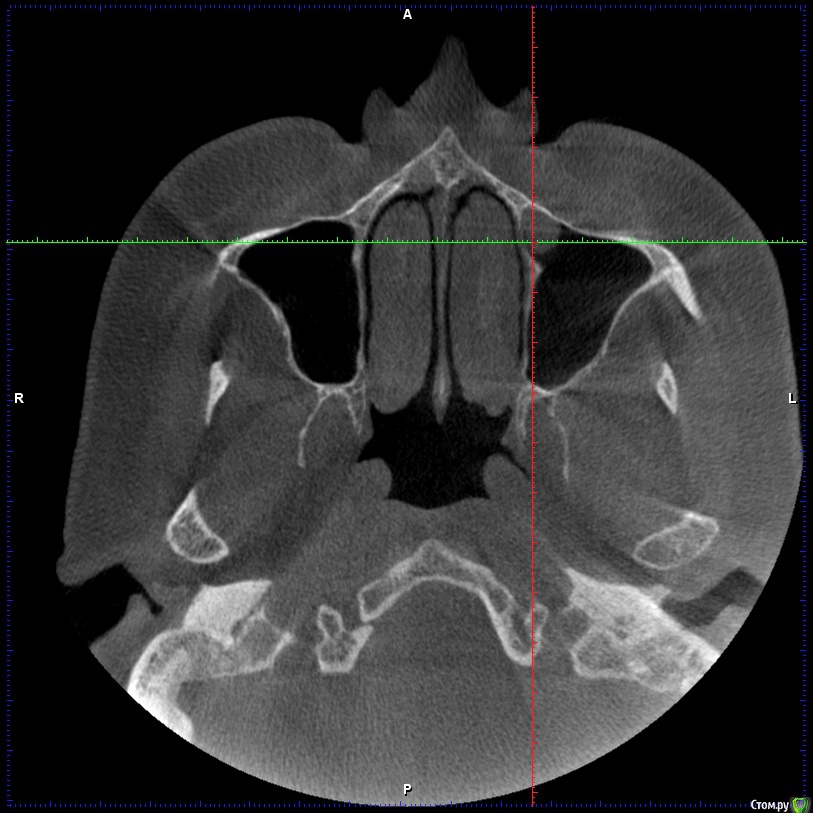

Aleksey_Mironov Опубликовано 11 января, 2018 Автор Поделиться Опубликовано 11 января, 2018 здравствуйте коллеги!! вот такой сюрприз..хочу сделать синус лифтинг.. что за образование можеть быть? Ссылка на комментарий

Борис80 Опубликовано 11 января, 2018 Поделиться Опубликовано 11 января, 2018 Не совсем уверен, тк недостаточно срезов видно, но я бы сказал насморк или что-либо подобное(это по поводу тени) и , что значительно неприятнее, это костная перегородка на дне пазухи Ссылка на комментарий

колесников Опубликовано 11 января, 2018 Поделиться Опубликовано 11 января, 2018 (изменено) Может образоваться перфорация мембраны. Делайте 2 окна Изменено 11 января, 2018 пользователем колесников Ссылка на комментарий